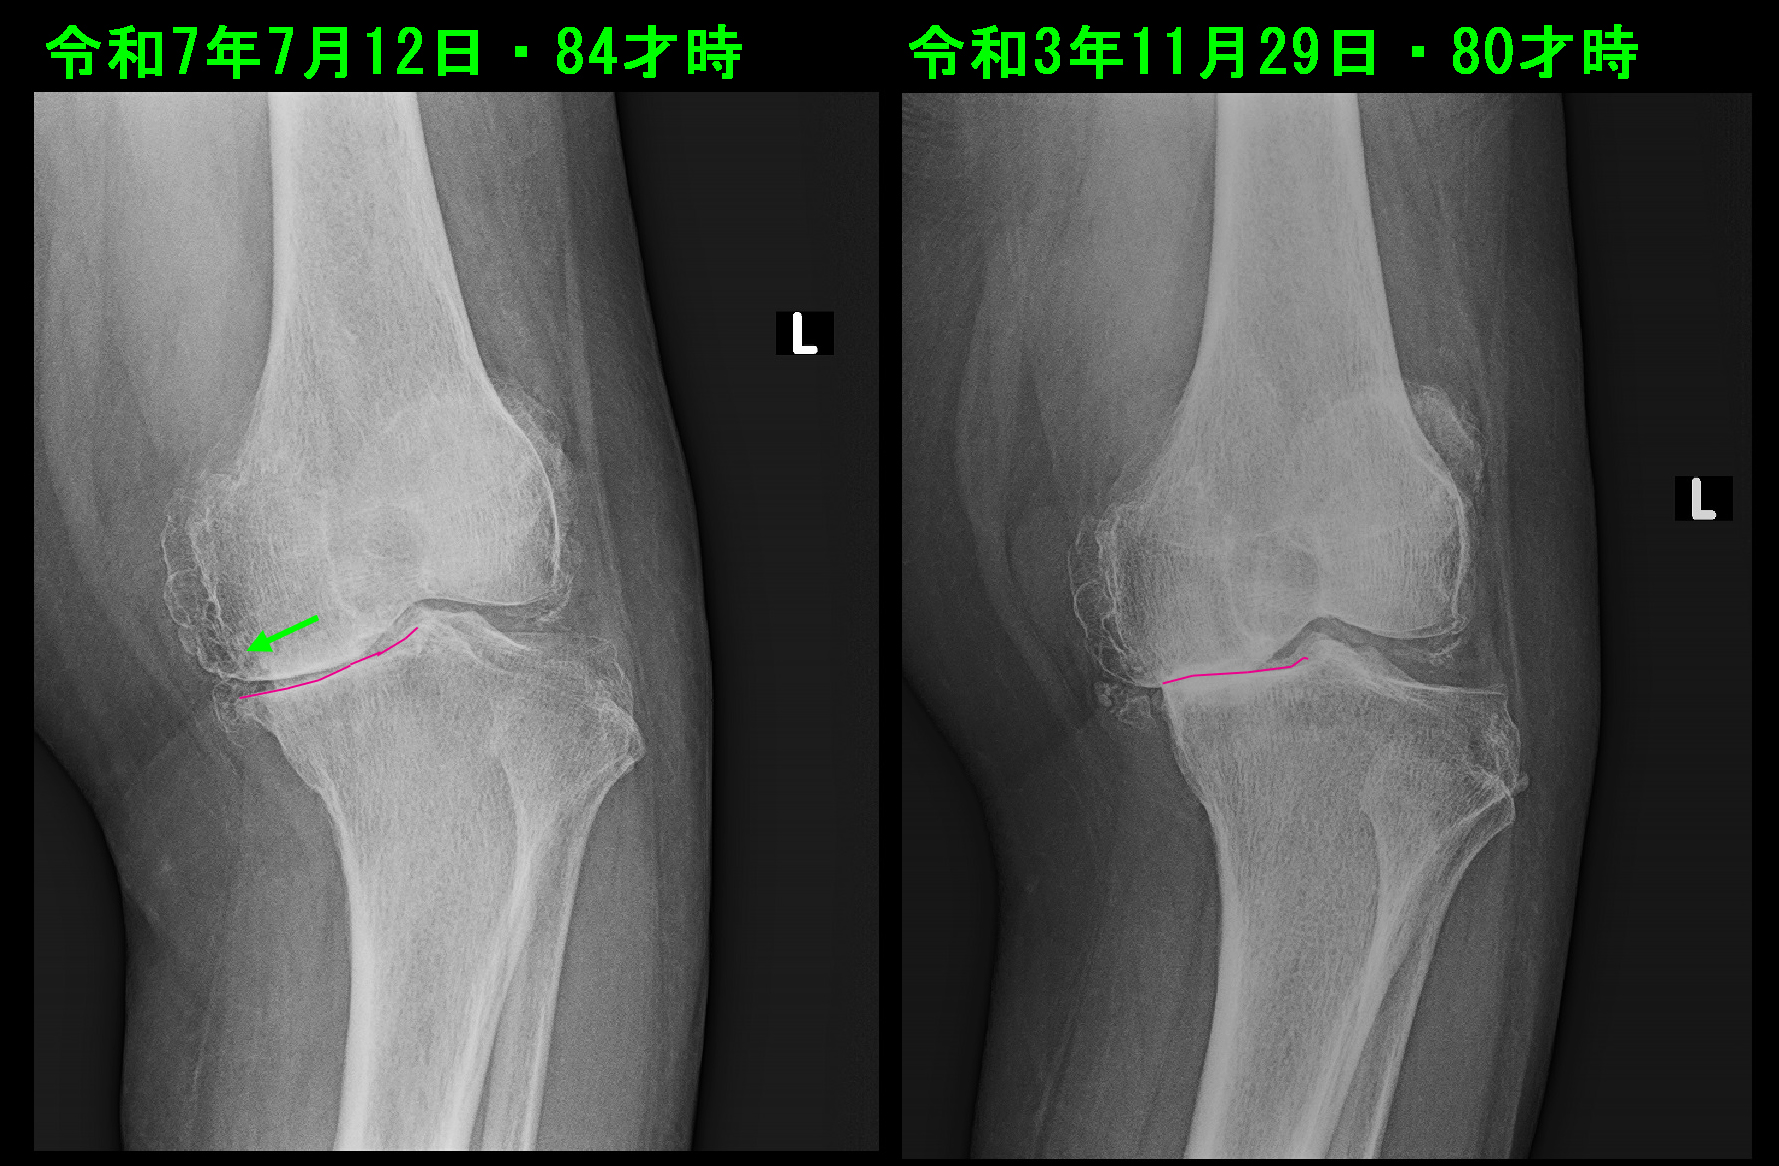

それに対して、令和3年11月29日80才で左膝痛で受診された女性です。初診時より左膝の内側の関節裂隙は消失しており、重度の変形性膝関節症です。保存的治療としてヒアルロン酸製剤関節内注入療法を断続的に継続していました。3年8か月後の令和7年7月の左膝関節のレントゲン像は、内側の関節軟骨が消失した状態は変わりありませんが、下腿側の脛骨の内側の骨の関節面が平坦な状態から摩耗して傾斜するようなラインとなっています。時々脛骨の内側部分がこのような傾斜するように摩耗する変形が進行していく方がいますが、このような変形では大腿部は体重がかかることで内側にずれる力が働きます(緑矢印)。このような変形ではこのホームページの「当院のリハビリテーション」のページの“86才女性 重度変形性膝関節症の不安定歩行のリハビリ”のような歩行状態となっていきます。膝痛が悪化するだけでなく、歩行が不安定となり、転倒のリスクも高まることになります。手術を受けなければ車イスの生活にならざるをえなくなってしまいます。注意を要する老化の変形です。その予防について明確な方針はありませんが、当院ではリハビリテーションを適応して、歩行の安定を図る試みを行っています。